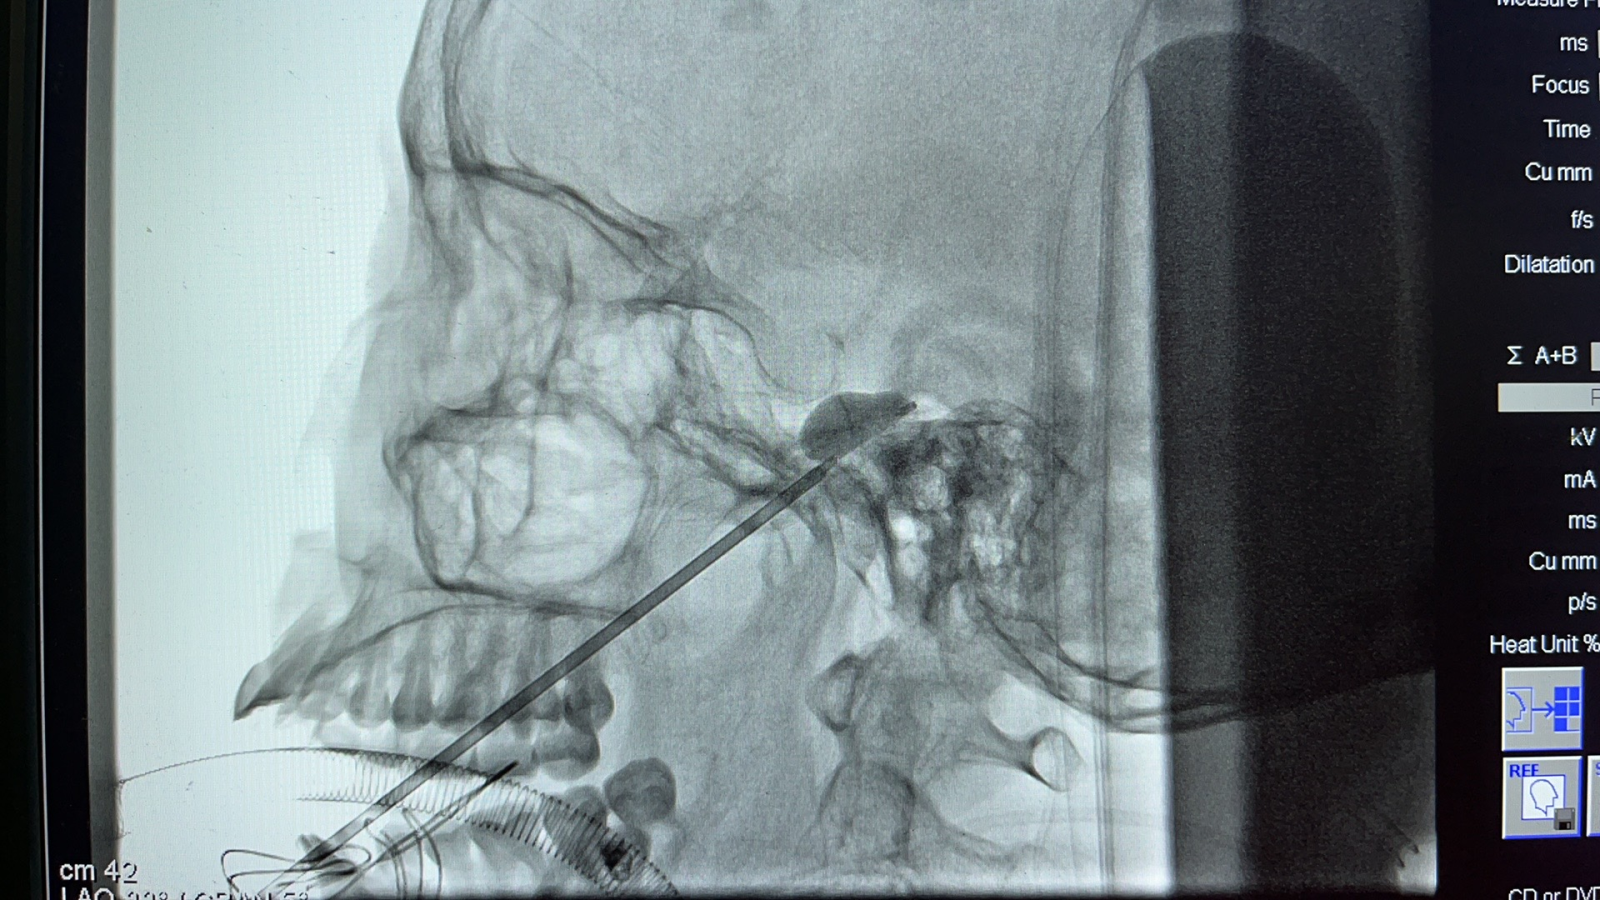

来自游仙区的何大娘,长期受面部疼痛困扰。“最初是偶尔痛一下”,她没有在意,想着忍一忍就过去了。后来疼痛越来越频繁,每次都像“电击火烧”一样难受。面部频繁的电击火烧样疼痛让何大娘苦不堪言。经人介绍,患者来到神经外科门诊就诊,神经外科副主任张海主任医师通过仔细询问病史,结合患者疼痛的特点、以往的检查及治疗情况,诊断患者为“三叉神经痛”。神经外科功能神经外科团队讨论后,决定为患者实施“经皮穿刺三叉神经半月节球囊压迫术”。高阳副主任医师实施手术,手术全程顺利。术后第二天,困扰患者多年的面部疼痛感消失了,术后观察三天,患者顺利出院。

张海主任医师介绍:三叉神经痛为常见的颅神经病变,发病高峰年龄在40岁以上,女性高于男性。主要表现为反复发作性的面部疼痛,突发突止,呈刀割、触电、灼烧及针刺样疼痛,虽是一种良性病变,不致命,但长期反复的剧烈疼痛严重影响患者生活质量,有时甚至伴有抑郁、焦虑等情绪。目前主要的治疗方式微血管减压术、经皮穿刺三叉神经半月节球囊压迫术、伽马刀治疗及射频消融等治疗方法。导致三叉神经痛等病因很多,常见原因为血管压迫,另外肿瘤、外伤、炎症及颅底畸形等均可引起三叉神经痛,根据不同病因,有不同的治疗方案。